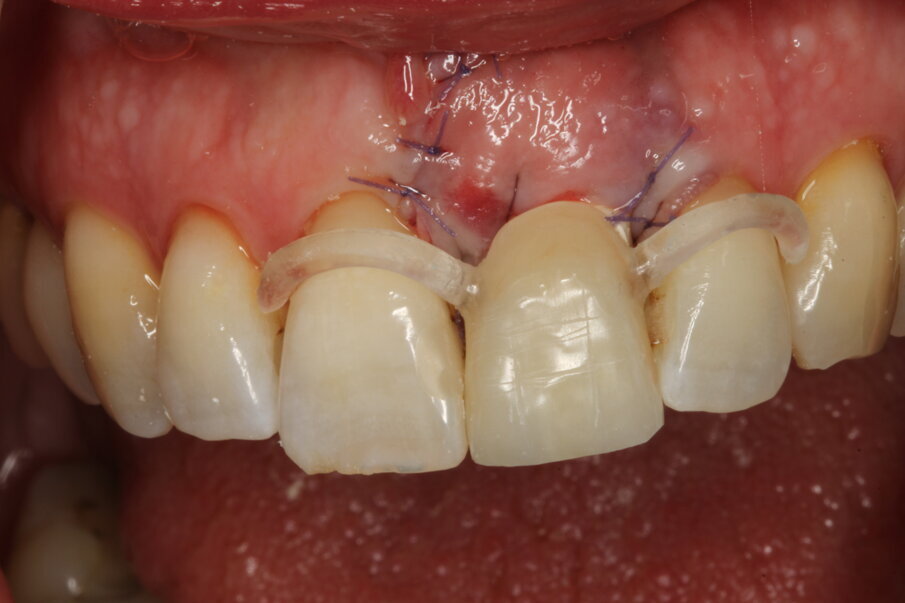

Local anaesthesia was performed with 2% mepivacaine with 1:100,000 adrenaline. Preventative antibiotic therapy with amoxicillin (1 g, b.d. for five days) was prescribed, aided by use of a 0.2 % chlorhexidine mouthrinse three times a day for one minute. The tooth was extracted and the sulcular epithelium removed with diamond burs. The milled surgical template (Figs. 12 & 13) served as a guide for the first 2 mm diameter pilot drill (Fig. 14). Thus, the planned depth, position and angulation of the osteotomy were obtained. The drill sequence was completed freehand, using tapered 3.0 and 3.4 mm drills. A Neoss Pro- Active Tapered Implant of 4 mm in diameter and 13 mm in length was inserted flush with the mesial/palatal/distal bone, motor driven up to a torque of 50 Ncm and then with a manual wrench (Fig. 15). The correct position of the internal hex was verified by checking the references on the implant driver, which ideally points in the buccal direction. Resonance frequency analysis with Penguin RFA (Integration Diagnostics Sweden) determined an ISQ value of 73/76. At this stage, a Neoss Esthetic Healing Abutment with a ScanPeg was connected to the implant (Fig. 16). A flap was then raised after a vertical incision of the frenulum and the expected buccal exposure of the implant neck was evident. Autogenous bone harvested from the drills was positioned directly on the implant surface (Fig. 17), followed by a bone substitute on top of it and on the buccal cortical bone (Fig. 18). This material was covered with a resorbable membrane (Fig. 19). The mobilised flap was then repositioned by rotating it coronally and fixed with single sutures (Fig. 20). The removable partial denture was adapted and delivered (Fig. 21). An immediate postoperative CBCT scan of 60 x 60 mm was performed, and it confirmed a perfectly centred implant position (Figs. 22 & 23).

Eight days after surgery, the patient reported that healing was uneventful and the prosthodontist removed the stitches. It has become the author’s standard protocol to perform an intraoral scan for implant position in this same session (Figs. 24 & 25). The specific and unique PEEK healing abutment used has an internal circular channel and on one side, normally positioned on the buccal aspect, a vertical rectangular slot (Fig. 26). After removing the PTFE tape used to plug this area during surgery, a ScanPeg can be positioned inside the healing abutment. This allows for a unique scanning procedure without removing the healing abutment, thus avoiding disturbing healing tissue or dislocating recently placed biomaterials. The producer provides libraries for STL files of the five different anatomical shapes—wide incisor, narrow incisor, canine, premolar and molar—that determine the basic profile of the gingival tunnel during healing.